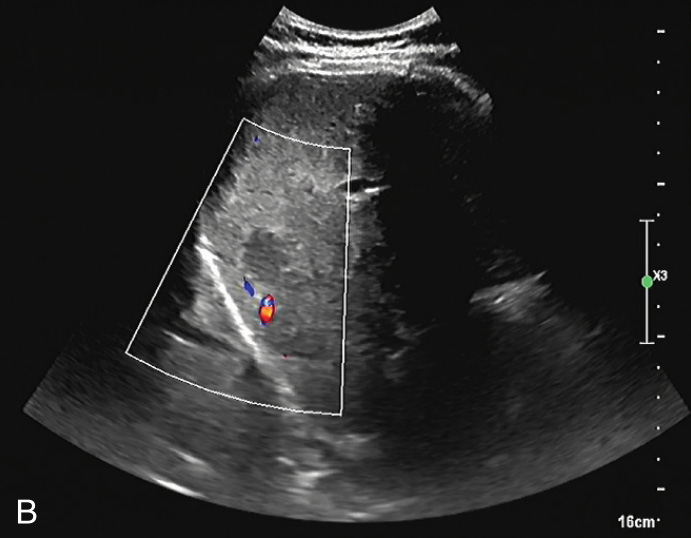

图1-5-1 肝细胞腺瘤常规超声图像

A.肝左外叶低回声结节,内可见条索状稍高回声,边界清晰;B.CDFI示其内可见点状血流信号